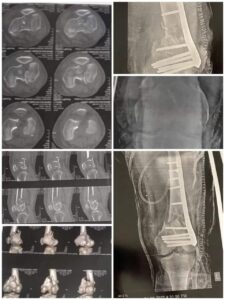

نجح الفريق الطبي في قسم العظام فى مستشفي كفر الدوار بقيادة د محمد فوزى رئيس القسم بالمستشفى وأطباء قسم العظام فى إجراء تثبيت لكسر عالي التفتت بمفصل الركبة واسفل عظمة الفخد لمريض بمستشفي كفرالدوار العام تم تثبيته بشريحة ومسامير مع الحفاظ علي سطح المفصل.

كما نجح قسم العظام في مستشفي النوبارية في اجراء عملية تثبيت كسر لعظام الكاحل الحالتين بشرائح و مسامير بقيادة د مصطفى درويش استشارى د.عادل نمير اخصائي العظام